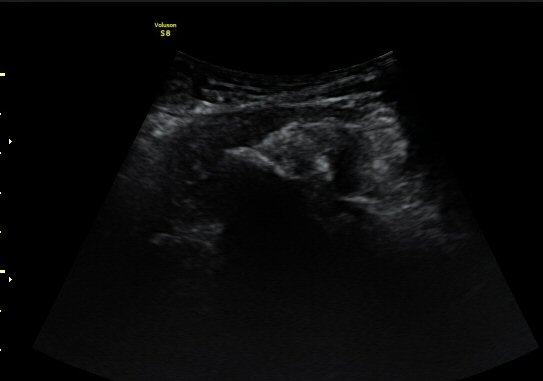

¾ûµ¢ÀÌ °üÀý Á¾´Ü¸é°Ë»ç¿¡¼­ ƯÀÌ ¼Ò°ßÀ» º¸ÀÌÁö ¾ÊÀ½(»çÁø 1).

ŽÃËÀÚ¸¦ ¾ûµ¢ÀÌ °üÀý ¿ÜÃø Á¾´Ü¸é°Ë»ç ½Ã ÀüÇÏÀ屨(AIIS)¿¡¼­ ¼®È¸È­¼º À½¿µÀÌ °üÂûµÊ(»çÁø 2, 3).